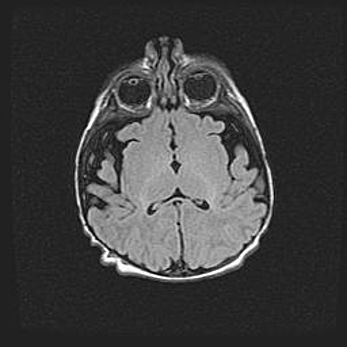

Церебральная ишемия II.

Возраст: 7 дней

Вес: 3350 г

Пол: женский

Окружность головы: 35 см

Срок гестации: 39 недель

Ишемия головного мозга – это состояние, которое развивается в ответ на кислородное голодание вследствие недостаточного мозгового кровообращения. У новорожденных она является следствием дефицита кислорода, что ведет к метаболическим расстройствам различной степени тяжести в тканях головного мозга, в том числе к развитию коагуляционных некрозов и гибели нейронов.